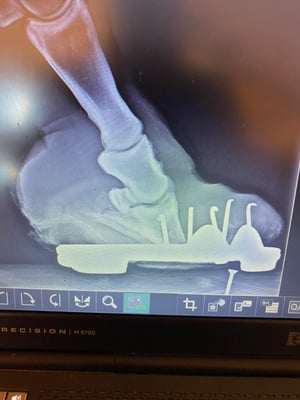

Die Zusammenarbeit von Veterinärtechniker und Tierarzt ist unerlässlich. Röntgenbilder sind absolut notwendig, um die Position des Hufbeines in der Hornkapsel zu erkennen und Sohlen- u. Wandstärke zu beurteilen. Dies ist

maßgebend für die Rehehuf- Korrektur und die Anfertigung des Hufschutzes, einem der Situation angepasster Klebebeschlag. Jeder Rehehuf ist anders, daher gibt es keinen Standardbeschlag. Der Klebebeschlag

• Hufrehebeschlag bei einer 34 Jahre alten Stute

Der Rehe-Huf wurde nach Sichtung der Röntgen Bilder korrigiert und ein reheadaptierter Duplo Beschlag angefertigt. Da das Pferd extreme Schmerzen hatte, wurde es durch den anwesenden Tierarzt sediert. Um dem Tier das Stehen während der Hufbearbeitung zu erleichtern wurde das Team von ANIMAL RESCUE (Dr. Christoph Peterbauer) zugezogen, welches eine unterstützende Hebevergurtung anbrachte.